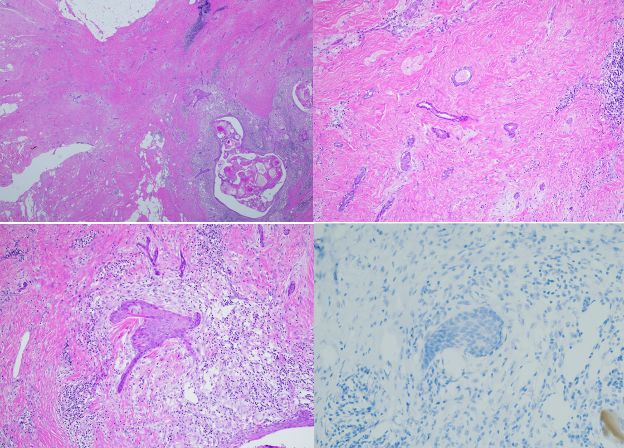

A woman in her 60s presented for a palpable mass in her left breast. She underwent a lumpectomy and excision of three axillary lymph nodes. X-ray of the specimen showed no evidence of calcifications. Histologic analysis of the specimen showed an infiltrative carcinoma with both glandular and squamous components (Figure 1). The lesional cells were negative for ER, PR, and HER2 immunohistochemistry. The diagnosis of low-grade adenosquamous carcinoma was made.

Figure 1. Low-grade adenosquamous carcinoma. Infiltrative glands and squamous cells (top left). Infiltrative glands (top right). Infiltrative squamous cells (bottom left). Immunohistochemistry for ER showing negative staining (PR and HER2 are also negative) (bottom right).